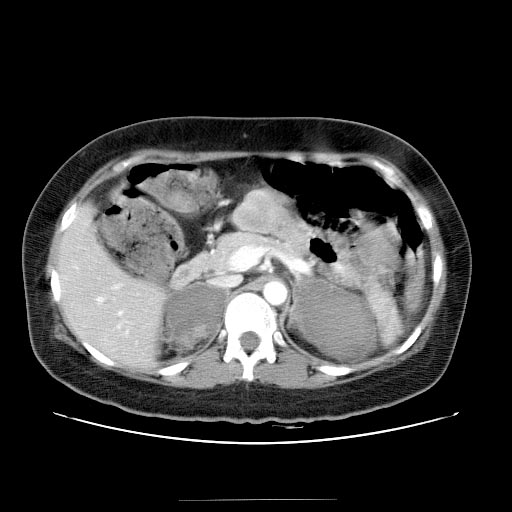

La tomografía abdominal proporciona imágenes detalladas del hígado y los órganos circundantes. En pacientes con cirrosis hepática, las imágenes de tomografía pueden revelar signos característicos de la enfermedad. Estos signos incluyen la presencia de cicatrices hepáticas (fibrosis), agrandamiento del bazo (esplenomegalia), acumulación de líquido en la cavidad abdominal (ascitis) y cambios en la morfología del hígado.

La cirrosis hepática puede llevar a una serie de complicaciones graves, como la formación de varices esofágicas, trombosis de venas hepáticas y hepatocarcinoma (cáncer de hígado). La tomografía es útil para detectar estas complicaciones y determinar si se requiere tratamiento adicional, como la colocación de un stent para las varices esofágicas o la evaluación de la extensión del cáncer de hígado.